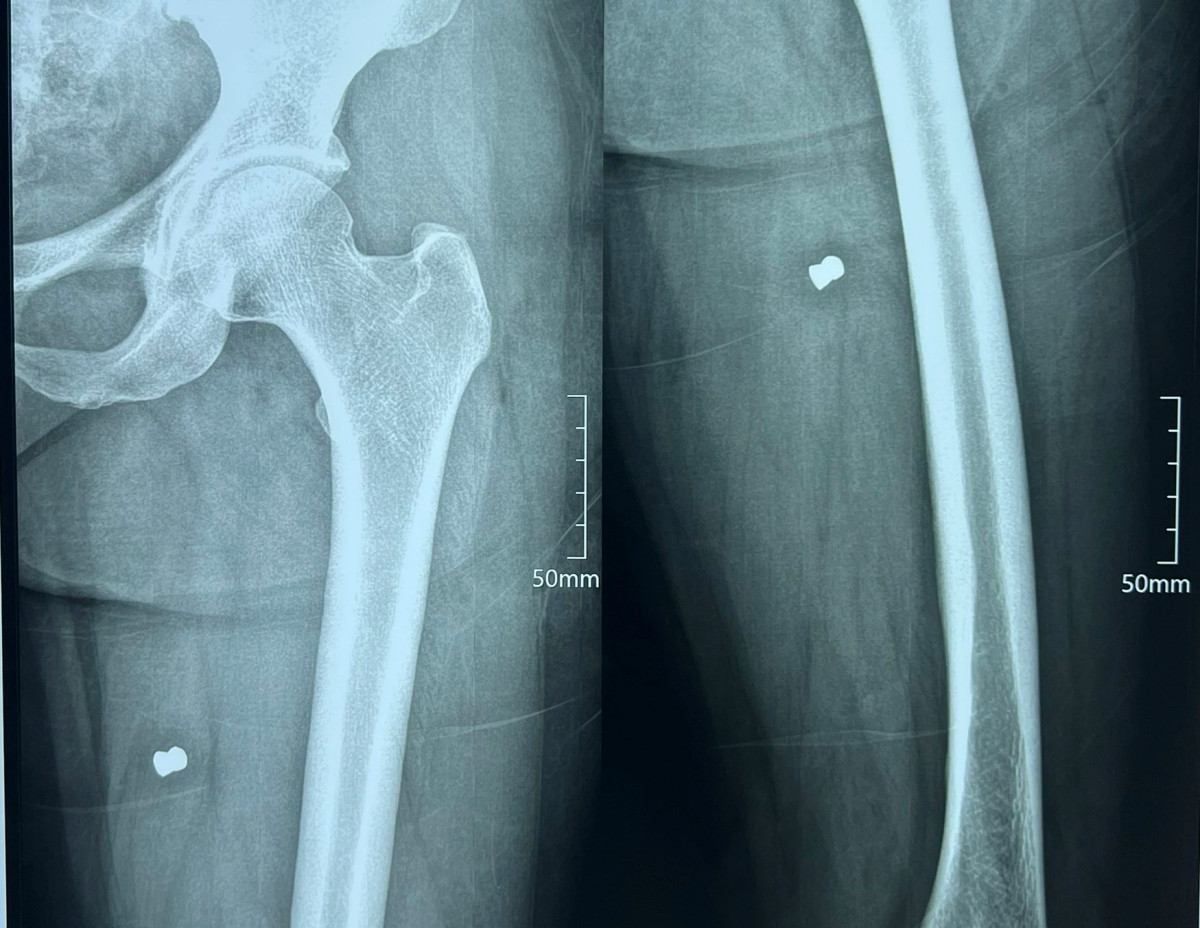

Người dân sống gần khu vực nghe tiếng súng nổ chạy đến và đưa hai chị đi cấp cứu tại Bệnh viện Đa khoa Phúc Hưng. Kết quả chụp phim cho thấy cả hai người đều có đầu đạn trong đùi và bắp chân.

Đến 13h chiều cùng ngày, hai nạn nhân đã được phẫu thuật lấy đầu đạn ra khỏi cơ thể, sức khỏe tạm thời ổn định.